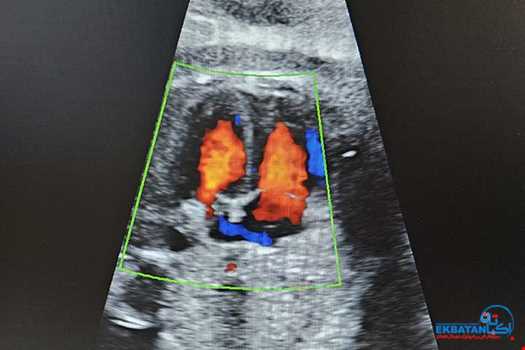

کالرداپلر قلب جنین

ناهنجاریهای قلب جنبن شامل اختلالات ساختاری ، عملکردی و ریتم قلب شایعترین آنومالیهای جنین می باشد که اکثر موارد با کالرداپلر پیشرفته قلب جنین در سن بارداری 18 هفته به بعد قابل تشخیص می باشد. انجام آن نیاز به آمادگی خاصی ندارد و همراه با آنومالی اسکن قابل انجام می باشد. در موسسه سونوگرافی اکباتان بررسی قلب جنین بوسیله دستگاه سونوگرافی کالرداپلر پیشرفته توسط متخصصین مجرب انجام می پذیرد.